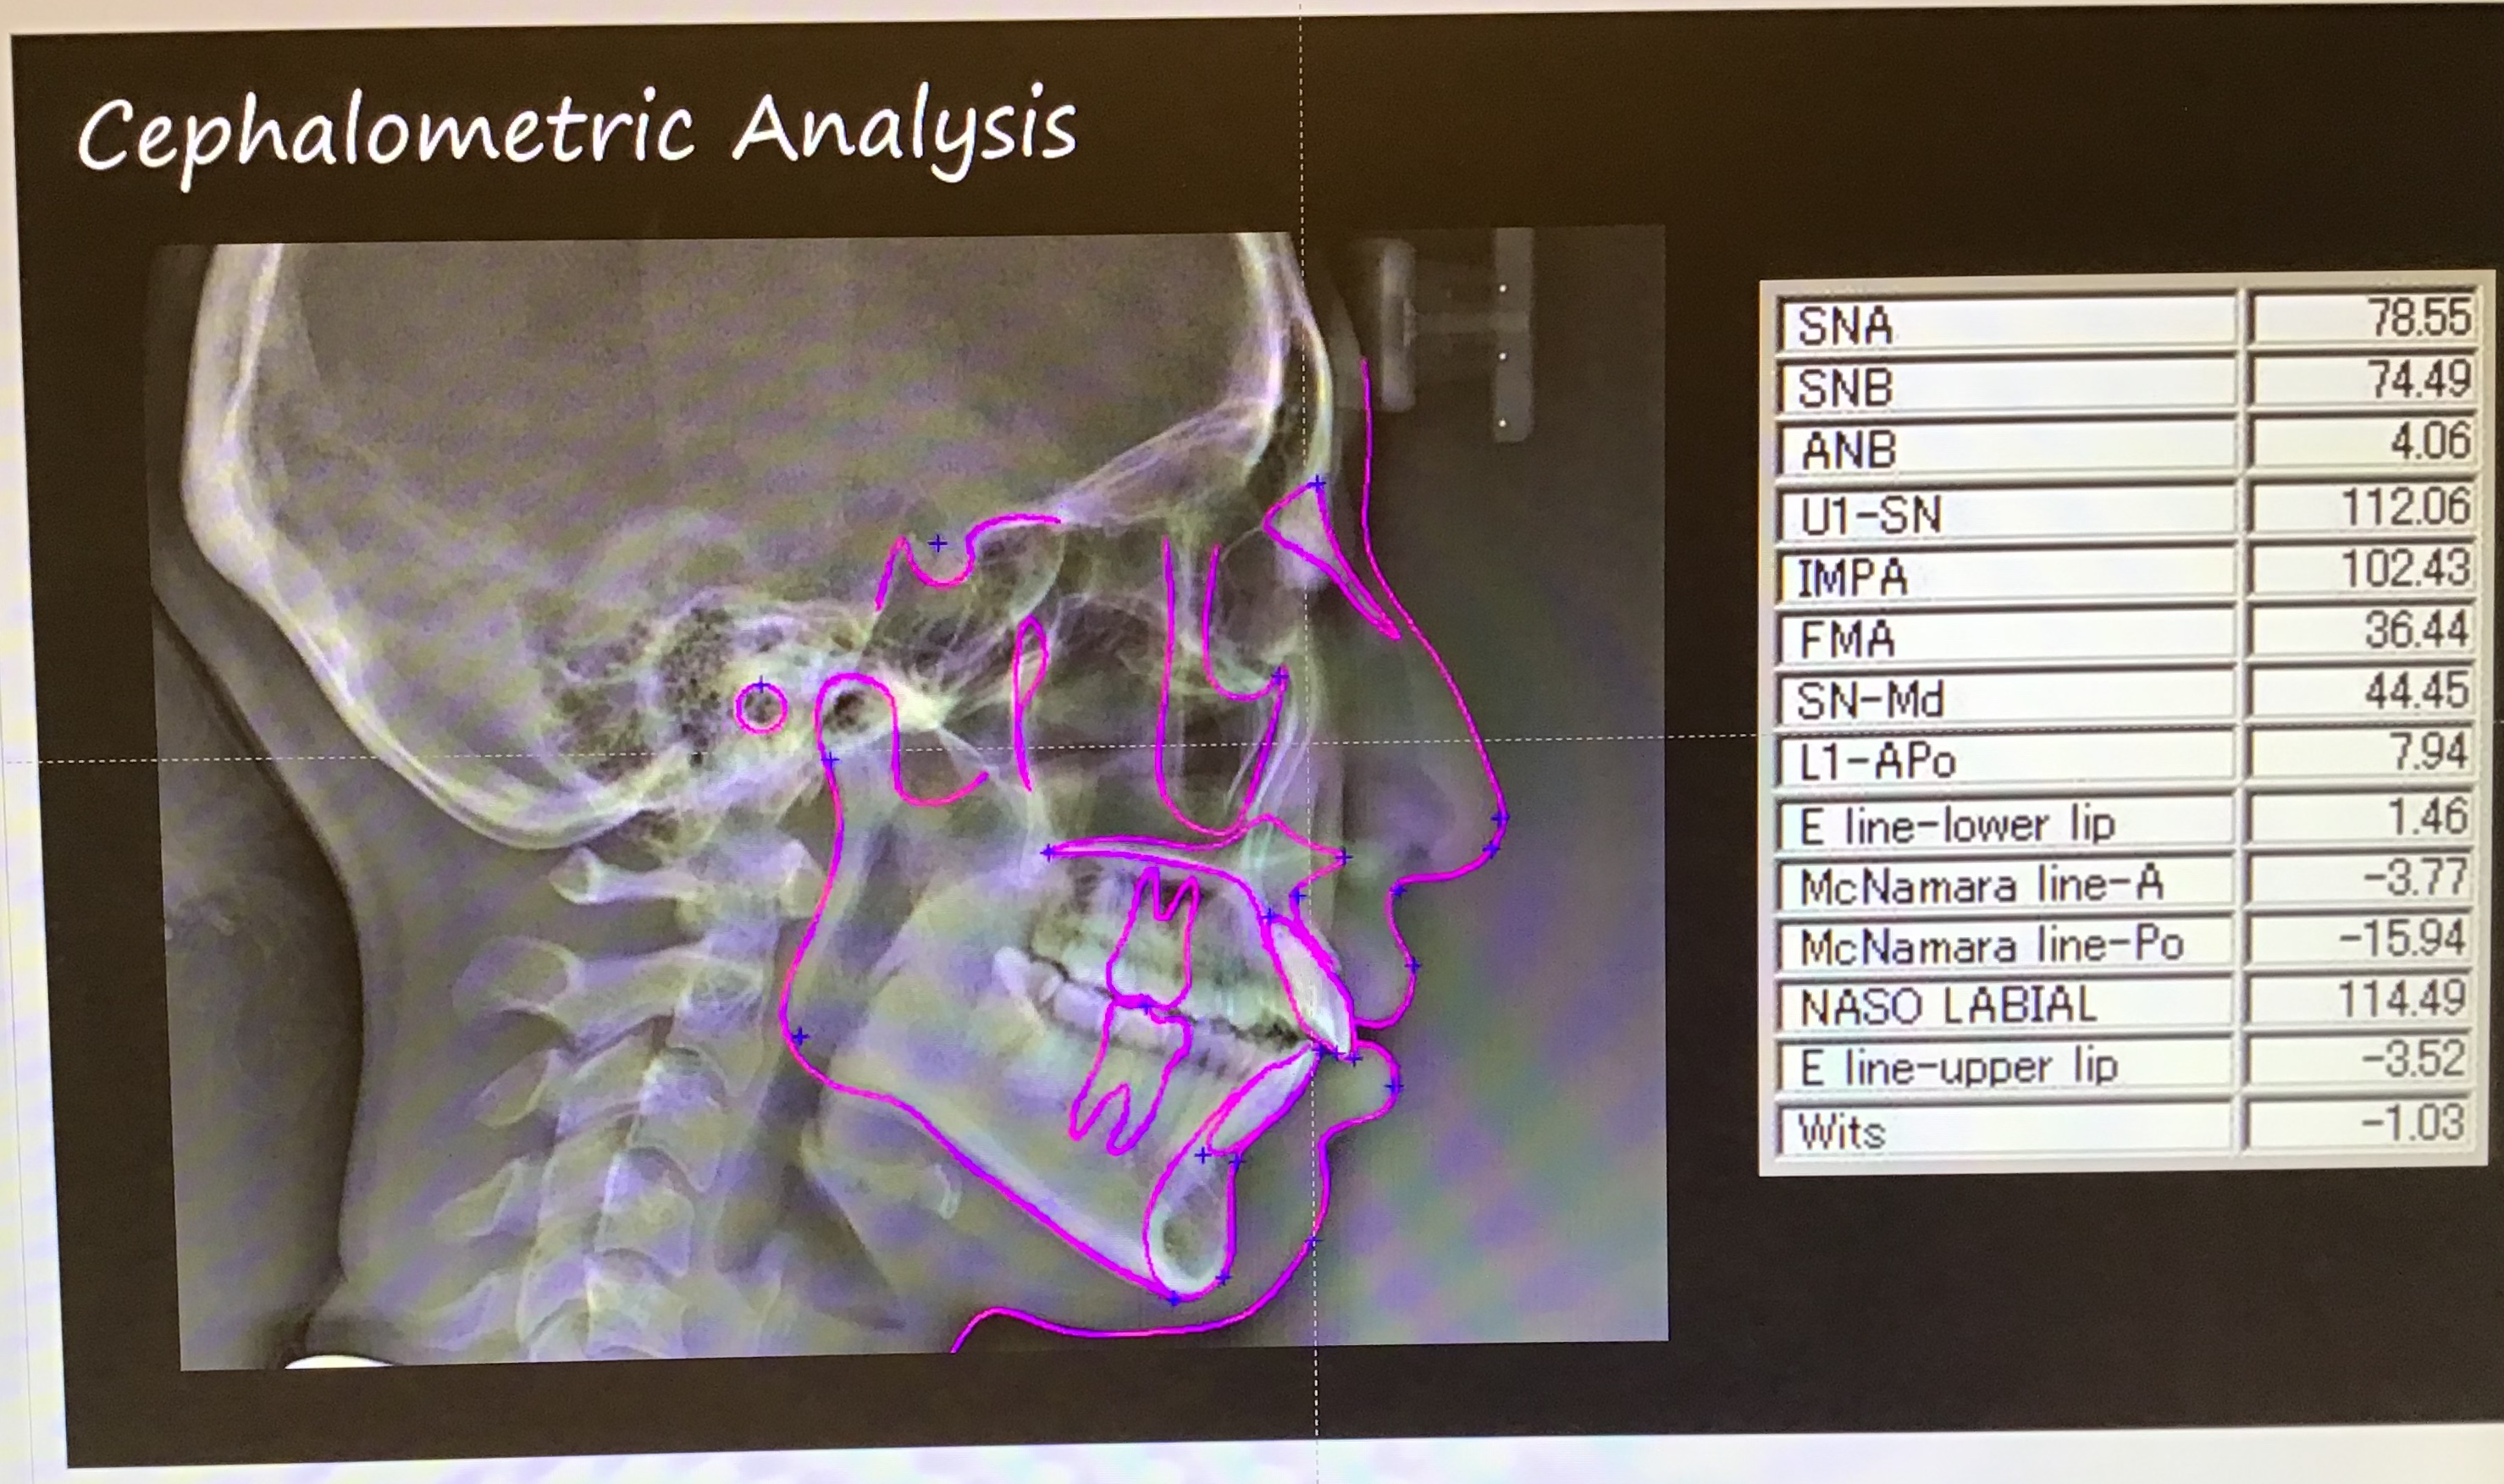

今回矯正するにあたって、執刀医である池田先生は治療内容や治療にかかる時間を細かくシュミレーションをしてから一つの資料にまとめて説明をしてくださいました。

ここに載せている画像は、私のデータをもとにシュミレーションが行われているものです。

この時点では、よくわからないですよね。ここからが池田先生の本領発揮!シュミレーションを照らし合わせながら分かりやすく説明をして下さいました。患者としてはこの説明を聞いくだけでも不安な気持ちも和らぐと思います。